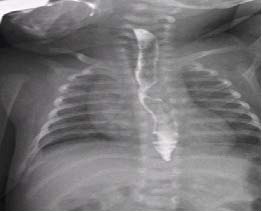

Una paciente gestante de 23 semanas con sospecha de malformación cardiaca fetal congénita fue derivada al servicio de cardiología pediátrica. Se realizó una ecocardiografía fetal, diagnosticándose un arco aórtico derecho mediante el plano de Yagel: tres vasos- tráquea. (Figura 1)

Figura 1. Ecocardiografía Fetal